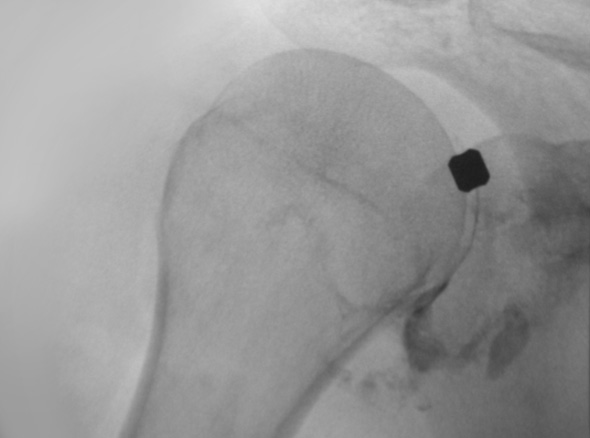

즉각적으로 통증을 완화해주고 어깨의 가동범위를 개선해주는 시술입니다.

주사 치료, 도수 치료 등을 하였으나 증상이 지속되는 경우

극심한 통증으로 스트레칭이 불가한 경우

정상 상태로 회복되는 걸리는 시간과 통증을 최소화 하고 싶은 경우